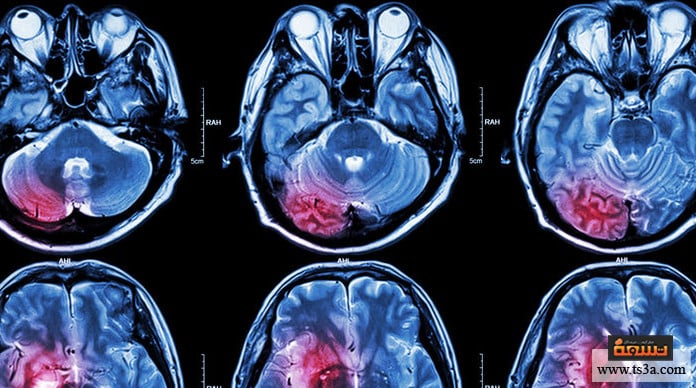

ينتج التهاب الدماغ لدى الأطفال عندما يصاب الإنسان بعدوى فيروسية أو بكتيرية تؤدي إلى التهاب الدماغ، وهذه العدوى قد تنتقل من خلال إنسان آخر أو من خلال لدغ البعوض والحشرات المختلفة التي بإمكانها نقل المرض، كما تنتقل في بعض الأحيان عبر تناول الأطعمة الملوثة؛ وعلى الفور يظهر الأثر على الدماغ ويبدأ في تحفيز الأنسجة المخية وجعلها تلتهب بشدة؛ مما يؤدي إلى تدمير الجهاز العصبي في المخ ويحدث بعض النزيف الداخلي وما يترتب عليه من أضرار كبيرة.

نظرًا لأن حالات التهاب الدماغ الياباني منتشرة بكثافة في مناطق جنوب شرق آسيا وتحديدًا في اليابان، فإنه من الشائع اعتبار أي شخص يعيش في هذه المنطقة أو سافر منها أو إليها أنه من المصابين بهذا المرض؛ لا سيَّما بعد الفيضانات التي تنقل مسببات المرض لتطوف مختلف أنحاء البلاد، ولكن زيادةً في التشخيص والفحص والتأكد من إصابة الحالة من عدمه يتم إجراء اختبارات مصلية تشمل للسائل الدماغي وتحديدًا ذاك السائل النخاعي الموجود بالمخ لضمان التعرف على إصابته بالفيروس من عدمه، كما أن الطب الحديث وفر الوسائل الطبية التي بإمكانها تتبع التهابات الدماغ والتعرف على الإصابة بالمرض أو عدمه من خلال فحص متلازمات الالتهاب الحاد الذي يصيب الدماغ في حال كان الفيروس قد تمكن من الشخص.